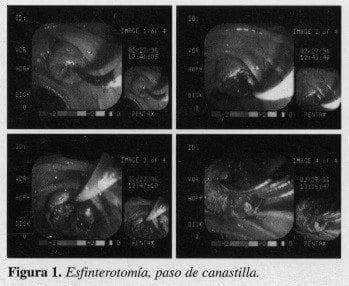

Las coledocolitiasis (83 casos) que no tenían cirugía previa fueron 61 (73.4%), y las que tenían algún tipo de cirugía previa, fueron 22 (26.5%). Las colangiografías postoperatorias fueron 48; éstas tenían los siguientes hallazgos: litiasis, 22 (45.83%); vías biliares dilatadas, 9 (18.75%); vías biliares normales, 7 (14.58%); filtraciones del conducto cistico, 5 (10.4%); neoplasias, 3 (6.25%); otras, 2 (4.16%) (filtración del canal de Luschka, hemobilia). (Figura 2).